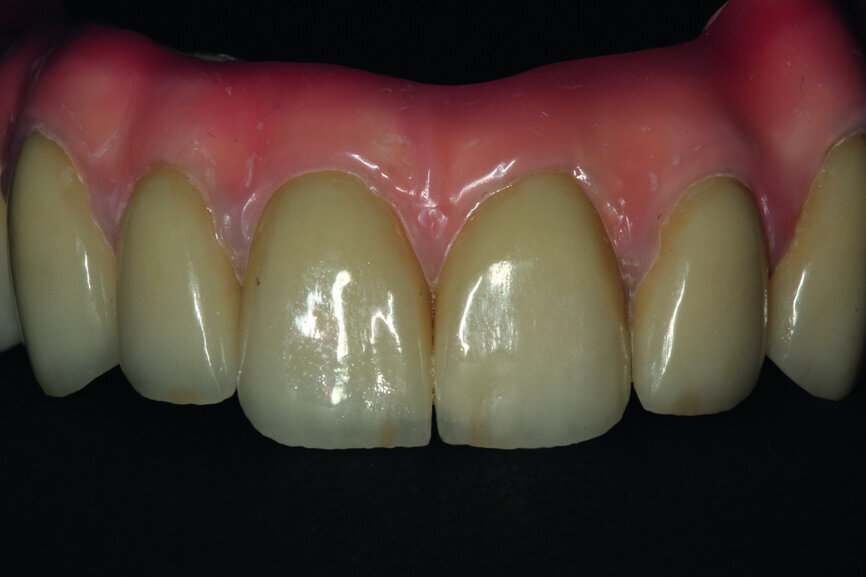

Fig. 14: Porcelain crowns based on a model prior to veneering by means of a pink composite.

After this has been done, the next step consists in testing the almost ready-made crowns before the final glazing and before attaching it onto the model. As a result it is possible to make corrections, should they be necessary. Of course, one should check the proper match-up and the aesthetics on the model (Figs. 13 & 14).

After the model was analysed, we proceeded to analyse the fitting and the aesthetics in the mouth of the patient. Carrying out such a test makes a lot of sense, especially in a dynamic way, and by asking the patient to make various facial movements, such as smiles and grimaces, we can assess the properties of the course of the border line of the zenith of the teeth and the transition into a gingival garland. It is of real importance as at this stage that we can plan the process of covering the construction with pink porcelain or composite (Figs. 15–17).